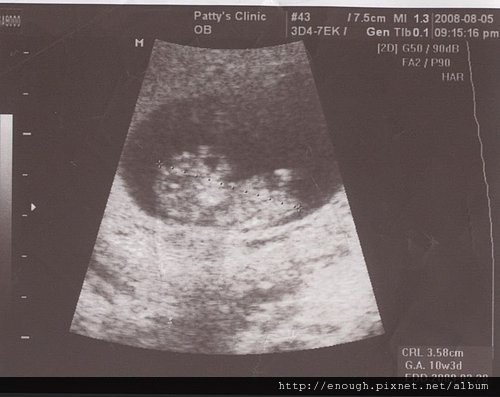

• 28週產檢的小牛

因為姐姐有太多事情要記錄,所以12/6的28周產檢延至今天才紀錄

產檢時間:12/6上午

地點:虎尾安安婦產科http://www.anan-obs.com.tw/index.html